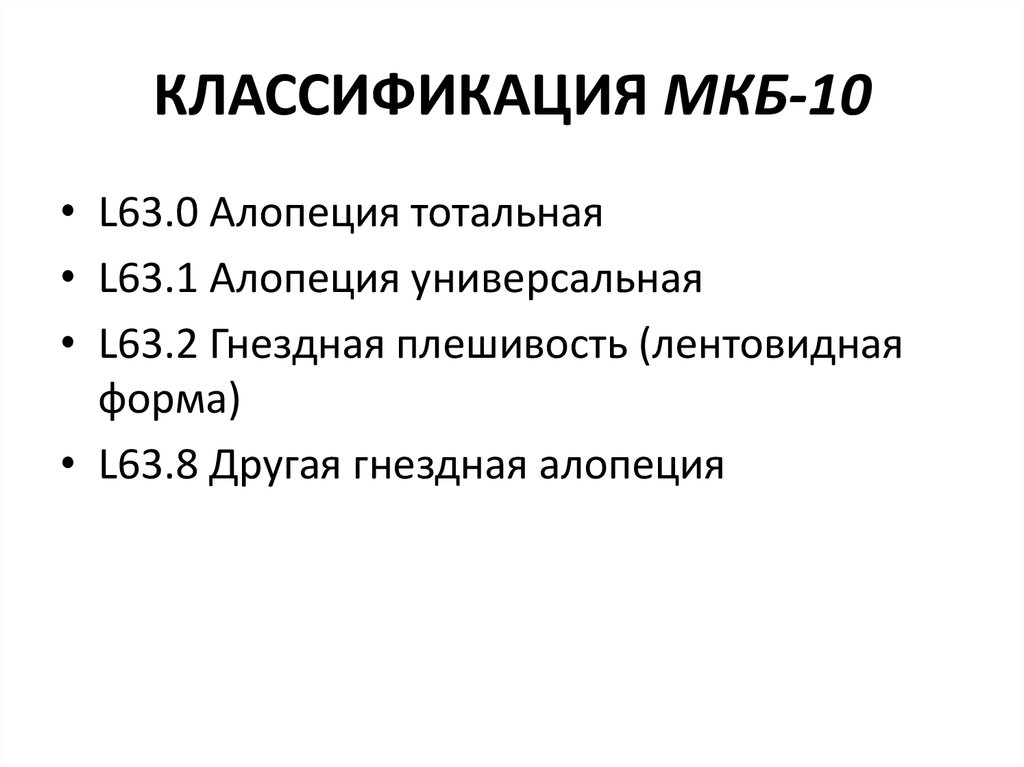

Код мкб 10 атерома головы

Код мкб 10 атерома головы 109 фото